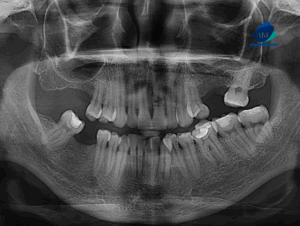

Paciente masculino de 8 años de edad acude al Instituto de Diagnóstico Maxilofacial – IDM (Miraflores) para evaluación imagenológica.En la radiografía panorámica (Figura 1), se